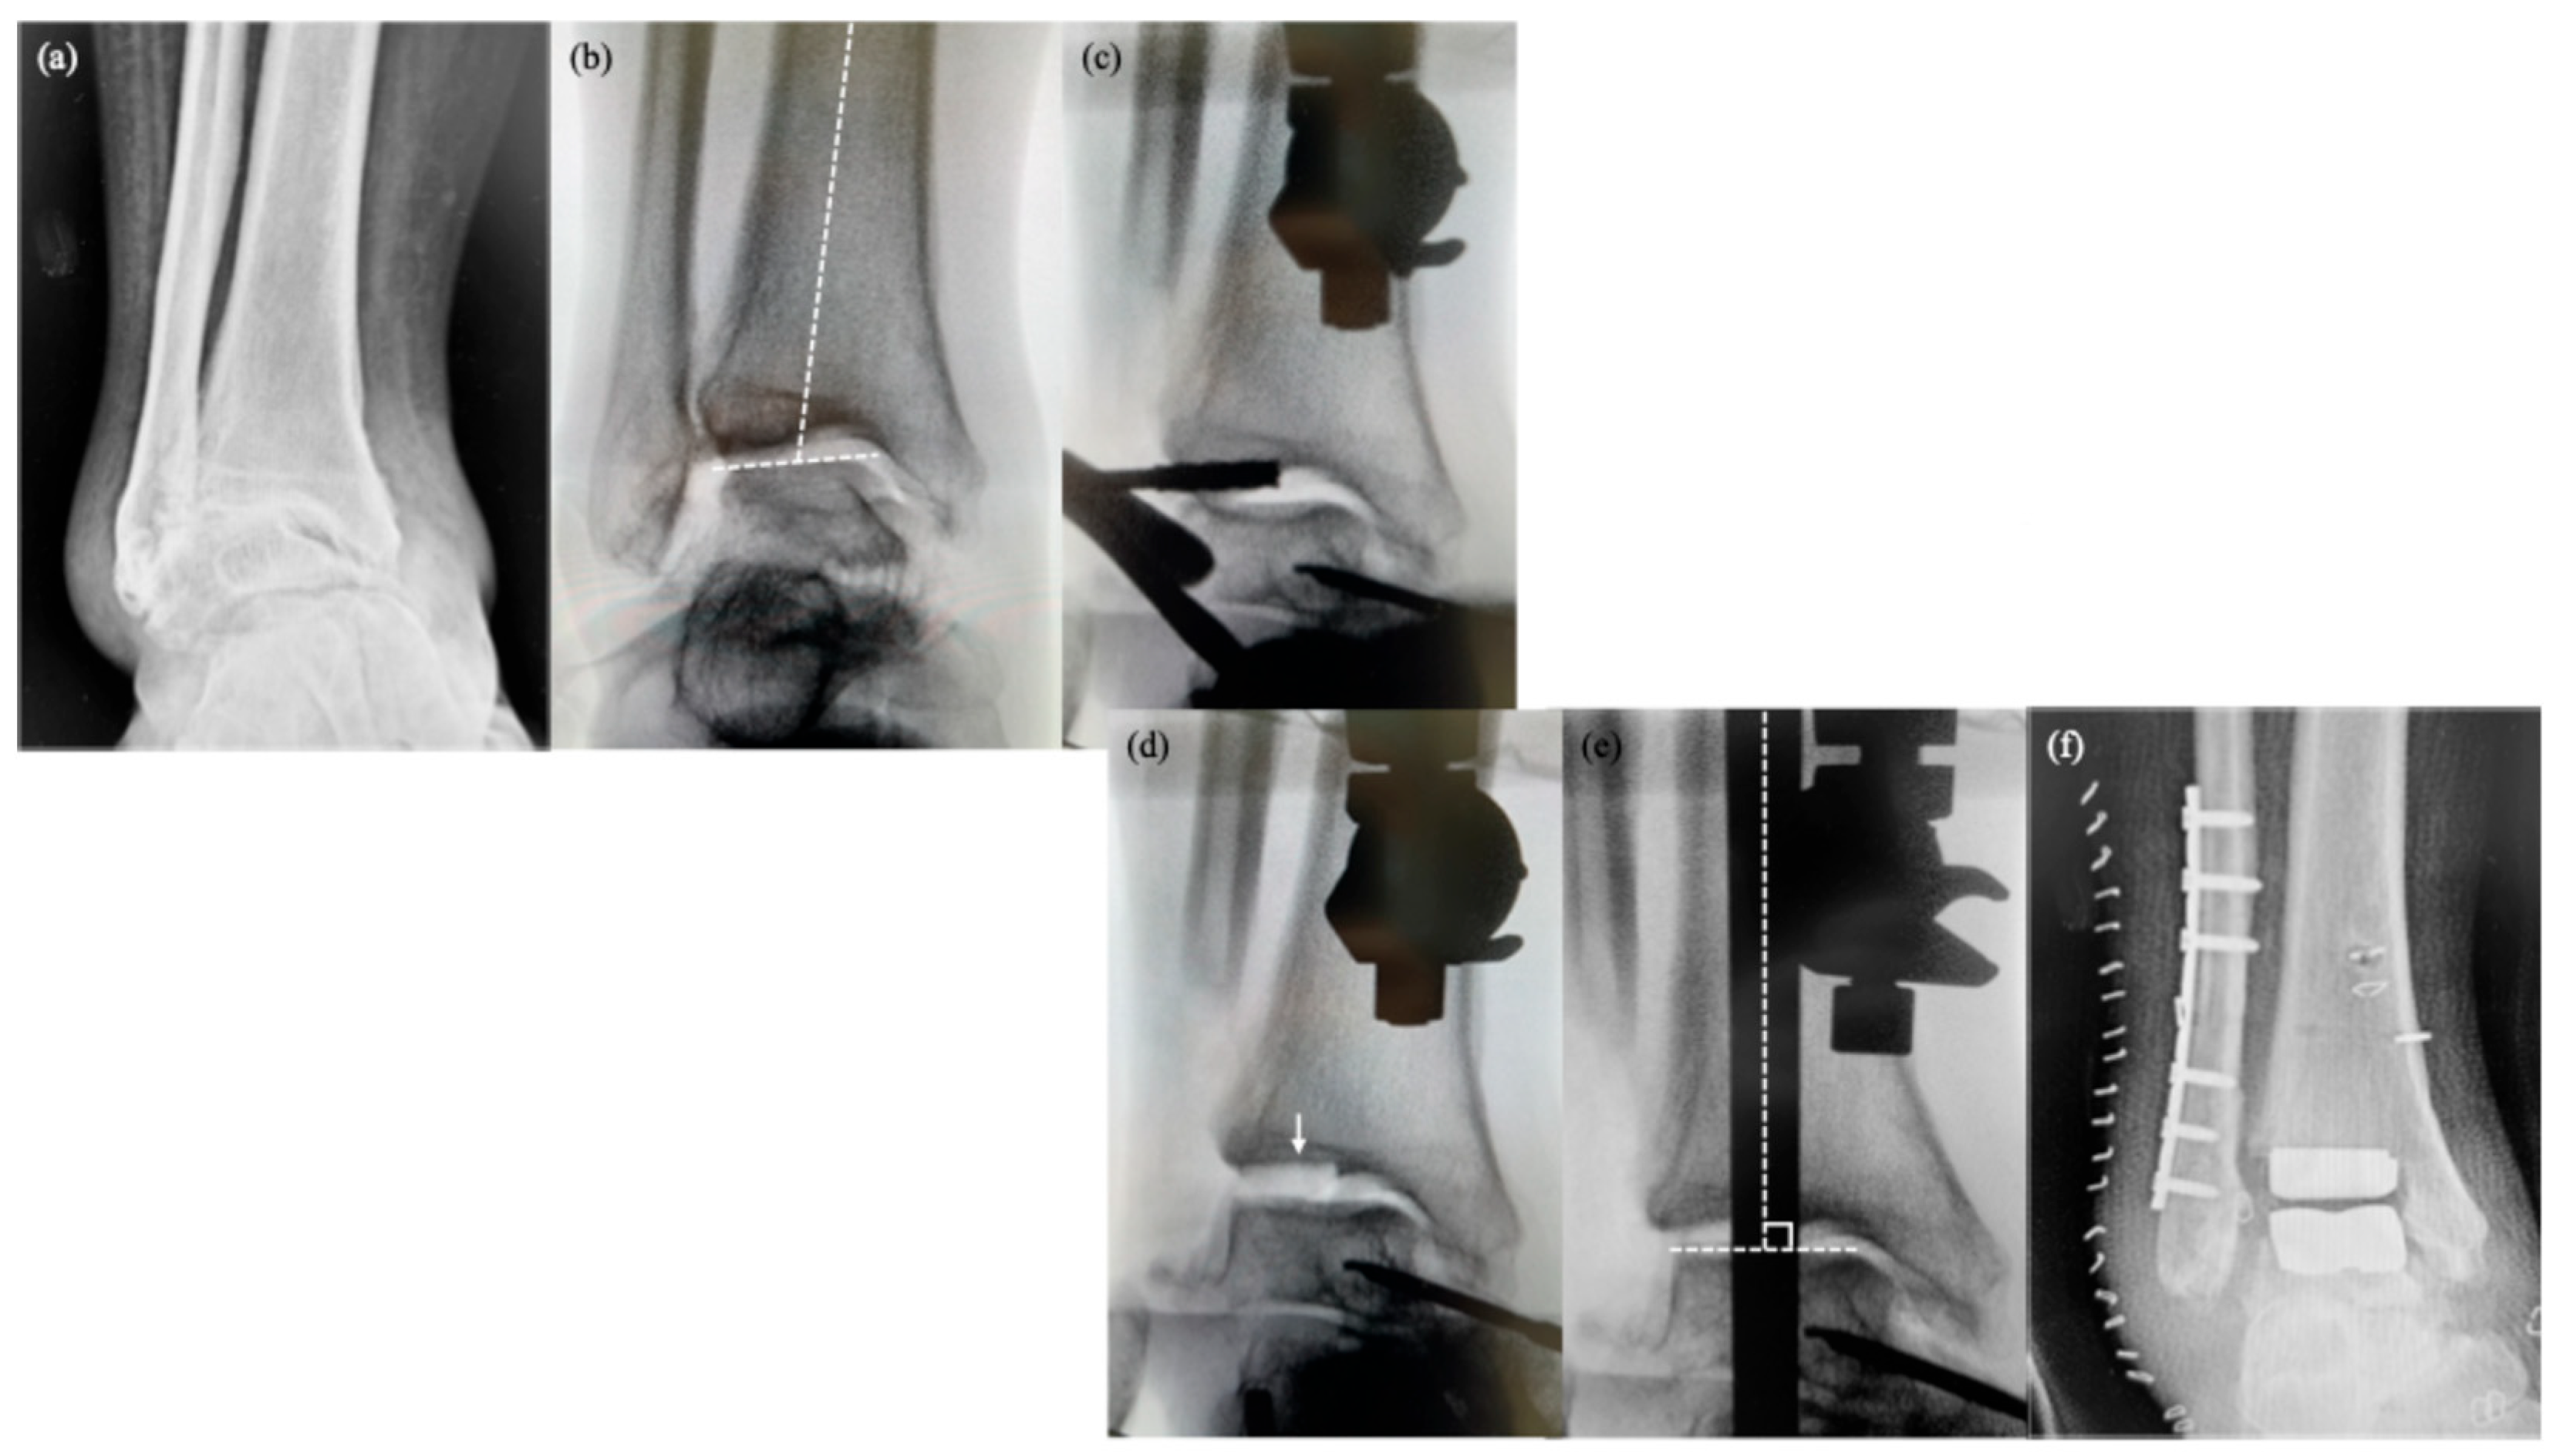

Figure 1.

Step-by-step demonstration of the “TIBIA #2 technique” for varus correction in transfibular total ankle arthroplasty. (a) Preoperative anteroposterior radiograph showing posttraumatic osteoarthritis with varus deformity. (b) Intraoperative fluoroscopic imaging. Even with attempts at varus correction, the bony conflict between the talar dome and tibial plafond prevents proper alignment. (c) Targeted resection of the lateral half of the distal tibia is performed through the “TIBIA #2” hole, originally designed for secondary cuts. (d) Resected lateral distal tibial fragment (arrow), confirming removal of the impinging bone. (e) With the impingement resolved, varus alignment is successfully corrected and the talar dome is positioned horizontally. (f) Postoperative anteroposterior radiograph demonstrates restored coronal alignment of the ankle joint.

The fibula was osteotomized according to the manufacturer’s instructions, and the lower leg was positioned on the alignment frame. A transosseous calcaneal pin was placed, and the sole was then secured to the footplate using calcaneal pin holders. Subsequently, the medial talar half-pin was inserted and fixed to the talar pin post on the footplate.

The TIBIA #2 technique was indicated when preoperative valgus stress radiographs showed that the talar dome cannot be corrected to a position perpendicular to the tibial axis due to bony conflict. A distal tibial pin was inserted from the anterior surface, approximately 5 cm proximal to the tibiotalar joint, and connected to the alignment frame. The silhouette guide was then positioned laterally, and the cutting block was adjusted until aligned with the talar dome. Once alignment was confirmed, the cutting guide was fixed in place, the silhouette guide removed, and bone cutting was initiated. A preliminary cut on the lateral distal tibia was performed through the TIBIA #2 hole to eliminate bony impingement between the lateral talar wedge and distal tibia. This “TIBIA #2 technique” utilized a guide hole originally designed for auxiliary resection after primary cuts with the TALUS and TIBIA #1 holes. Subsequently, the distal tibial pin was disconnected, and the alignment frame was manipulated into a valgus orientation to correct varus alignment. In cases with more severe deformity, the medial gutter was accessed anteriorly to perform a superficial deltoid ligament release and remove osteophytes. Fluoroscopy was used to confirm coronal alignment: on AP view, the talar dome was aligned horizontally and the tibia vertically. The ankle was distracted along the frame to allow appropriate bone resection while maintaining medial soft tissue tension (

Figure 1) [

8].

Standard bone cuts were subsequently performed according to the manufacturer’s guide, followed by trialing and implantation. The fibula was shortened and fixed with a plate or screws to address coronal deformity, and a Broström repair of the anterior talofibular ligament was performed before wound closure (

Figure 1). If dorsiflexion angle of the ankle joint was less than 10 degrees, additional Achilles tendon lengthening was performed. A tourniquet was employed as required and released after a maximum of 2 h.